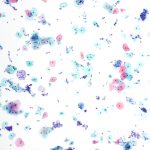

No Lubricant Control – 10x

Control vial

…shows superficial and intermediate cells evenly dispersed across the field of view. There is no visible evidence of lubricant or lubricant effect. Minimal degree of overlap and clearing is commonly seen in thin layer preparations.

4x

Control vial

…shows superficial and intermediate cells evenly dispersed across the field of view. There is no visible evidence of lubricant or lubricant effect. Minimal degree of overlap and clearing is commonly seen in thin layer preparations.

4x